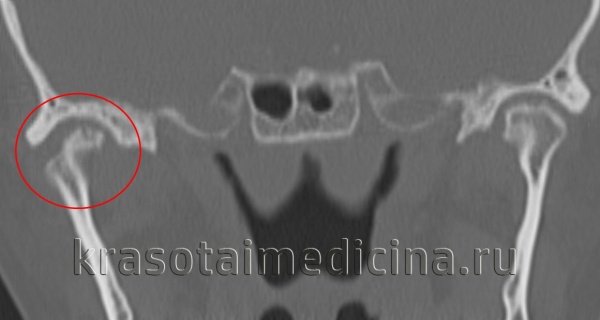

(Слева) При корональной КТ в костном окне у четырехлетней девочки, страдающей ювенильным идиопатическим артритом (ЮИА), визуализируются эрозии мыщелка нижней челюсти справа (эрозии существуют длительное время, края мыщелка неровные). Отмечается также расширение и уплощение суставной ямки.

(Справа) При МРТ Т1ВИ FS с КУ b корональной проекции у этой же девочки с ЮИА определяется выраженное контрастное усиление пораженного сустава, а также костного мозга правого мыщелка нижней челюсти, обусловленное его воспалением. Со стороны левого ВНЧС не определяется воспалительных изменений, мыщелок и суставная ямка не выглядят патологически измененными.